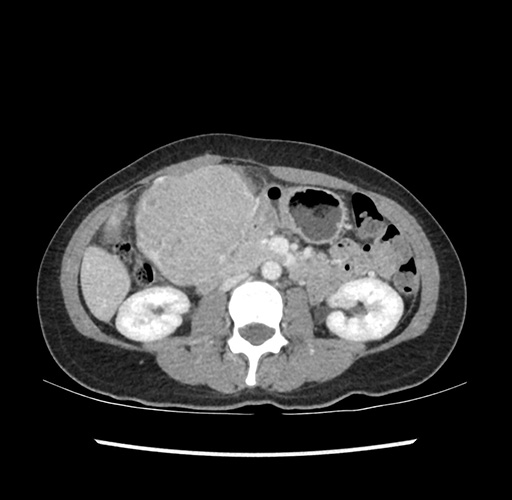

Imaging Analysis

Look through the patient's CT scan to identify any areas of concern for the necessary procedure.

Based on your CT findings, which issue(s) would give reason for "planned slowing down moment(s)" in this case?

Considering a standard left lateral sectionectomy procedure, what step(s) of the operation would you do differently in this case ?